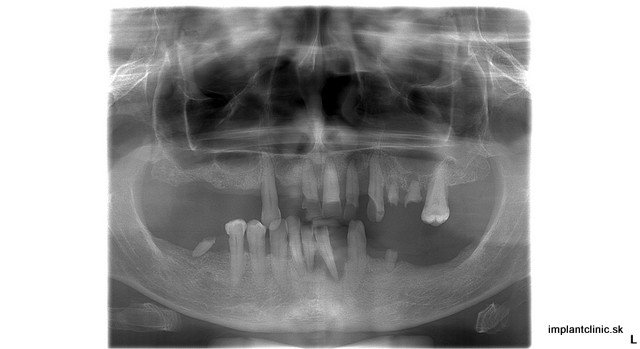

Ak vás trápia chýbajúce zuby alebo nosíte zubnú protézu, je možné, že ste už sa niekedy pristihli pri tom, že svoj úsmev schovávate. Fixné zubné protézy môžu byť pre mnohých ľudí nepraktické, pretože sa pri rozprávaní či jedení zvyknú pohybovať a v ústach často pôsobia neprirodzene. Ak je vám pomyslenie na to, že by ste mali zubnú protézu nosiť po zvyšok svojho života nepríjemné, máme pre vás riešenie. V súčasnosti čoraz viac ľudí volí zubné implantáty ako vhodné riešenie na obnovu ich úsmevu.

Zubný implantát je v súčasnosti najpopulárnejšou a najúčinnejšou alternatívou pre ľudí, ktorí z nejakého dôvodu prišli o svoj zub. Jedná sa o malú skrutku, ktorá sa vloží do čeľustnej kosti a plní tak funkciu zubného koreňa, na ktorý sa potom nasadí nová zubná korunka. Vyrába sa z titánu alebo iných materiálov vhodných na použitie v ľudskom tele, a preto nevyvoláva žiadne alergické reakcie. Na rozdiel od fixnej protézy je zubný implantát trvalým riešením pri náhrade jedného alebo viacerých chýbajúcich zubov. Okrem toho pôsobia veľmi prirodzene a plnia funkciu vašich vlastných zubov.

Zubná protéza slúži ako pomôcka nahrádzajúca chýbajúce zuby, ktorá je snímateľná a v ústach nedrží nastálo. Je to ekonomicky prístupnejšie riešenie pri väčšom počte chýbajúcich zubov.

Zubné protézy, vyberateľné náhrady zubov môžu byť cenovo dostupnejšou náhradou zubov v porovnaní so zubnými implantátmi. K zubnej protéze treba ale pripočítať aj špeciálne čistiace prostriedky, kefky, fixačné lepidlá a krémy, prípadné opravy a úpravy zubných technikom. Zubné protézy nazývané tiež ako žaby sa zvyčajne musia vymieňať každých 7 až 15 rokov, v porovnaní s priemernou životnosťou zubných implantátov cca 25 rokov. Preto sú zubné implantáty považované za dlhodobú investíciu do svojho zdravia.